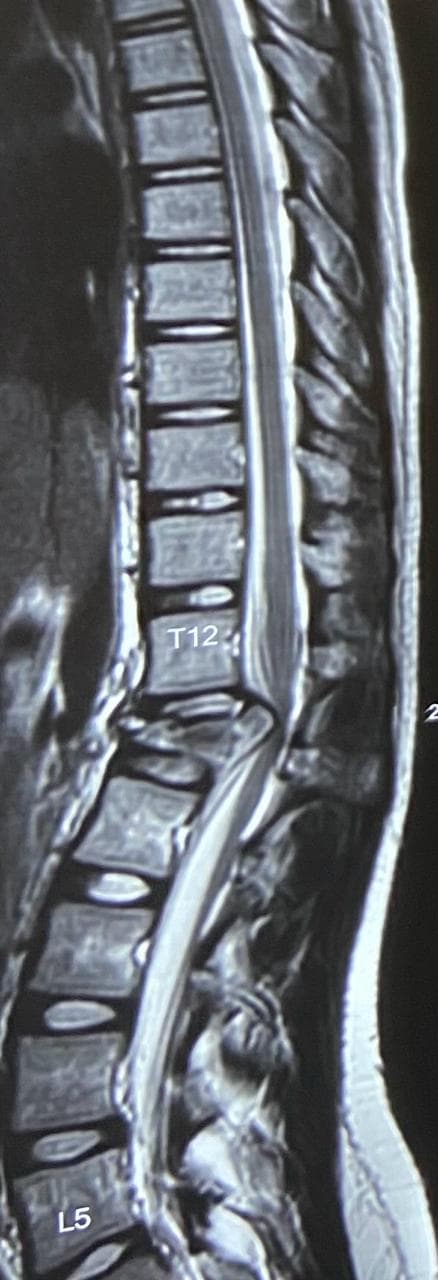

Spine fractures

A 17-year-old girl was brought to us after a fall from the first floor of her house. She had sustained a severe injury to her spine and was unable to walk at the time of admission. X-rays and MRI revealed an L1 burst fracture with compression over the spinal cord. On clinical examination, she had paraparesis—weakness of both lower limbs—with significant difficulty in standing and moving. The family was deeply worried as her ability to walk again was uncertain. Given the severity of the spinal cord compression and the risk of permanent neurological loss, she was taken up for emergency posterior stabilization and decompression of the spinal cord